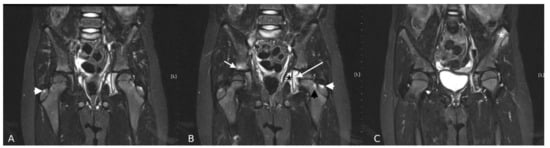

3. Results